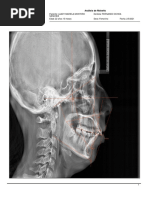

Este documento presenta un análisis de Ricketts que evalúa 31 parámetros craneofaciales y dentales agrupados en 6 campos. Cada parámetro incluye un rango normal y el valor del paciente. El diagnóstico final resume las desviaciones del paciente respecto a las normas y su impacto en la estética y función dental y facial.